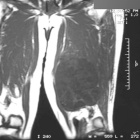

68 year old male with mass noted in left leg four weeks ago

Zoom image: Radiological image Radiological image.